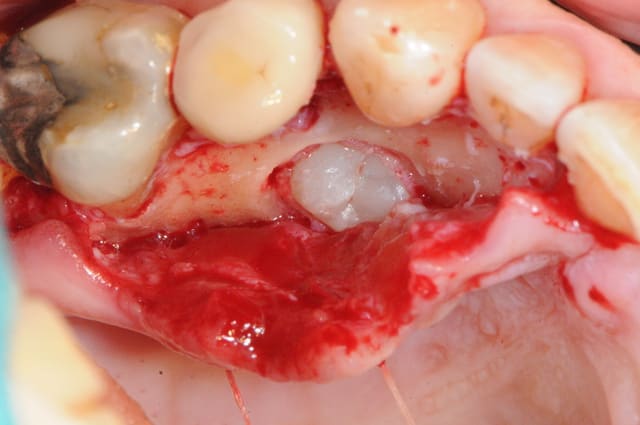

31/03/2013 à 22h31

1 le trou !

2 les trous !

3 les trous et l'implant

(un axiom PX pour la stabilité...)

4 comblement

5 dent provisoire

6-7 sutures